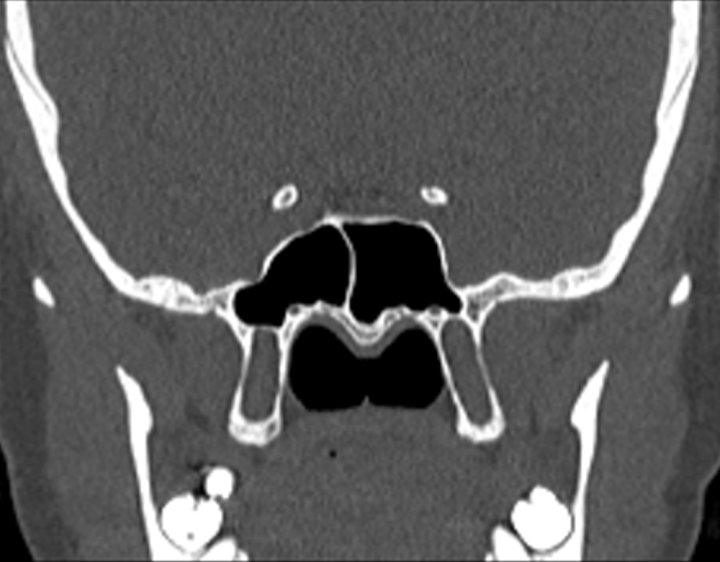

Click any image for labels.